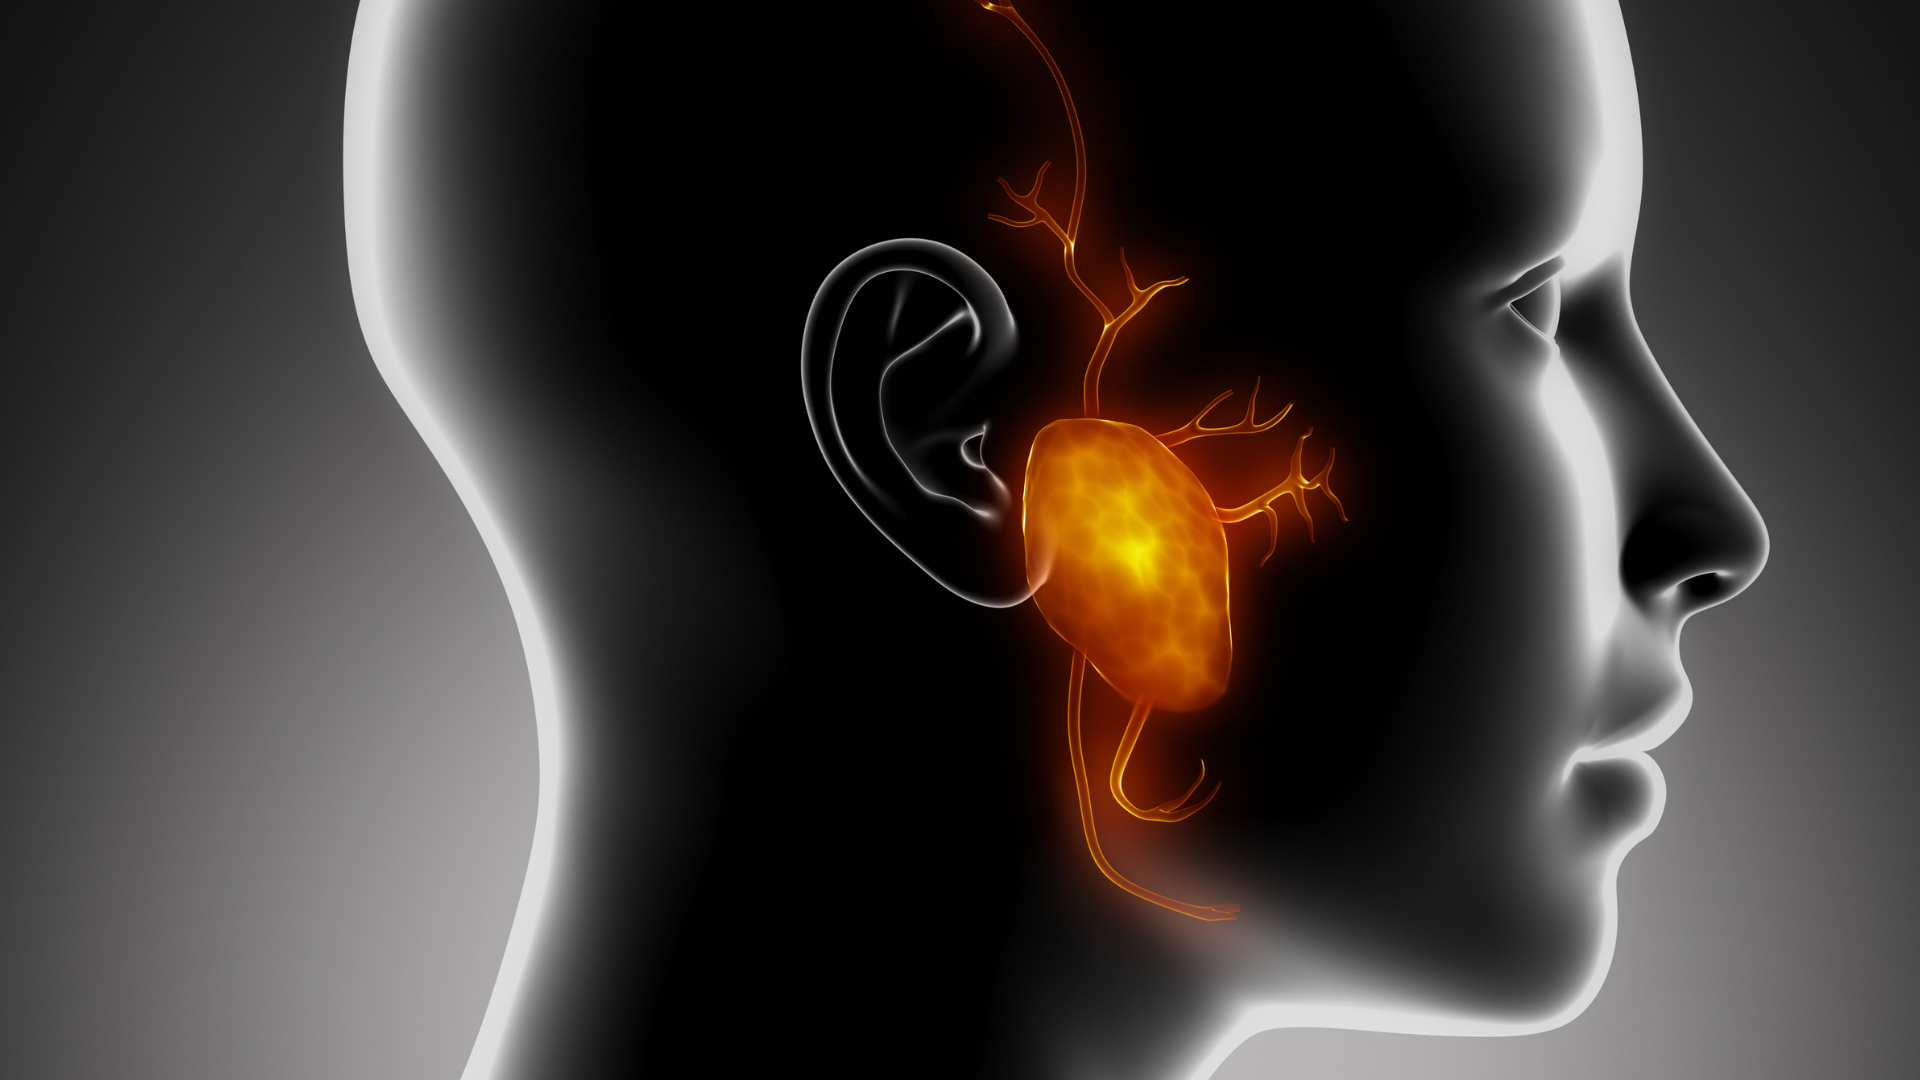

Patologías en Glándulas salivales

Las patologías de las glándulas salivales incluyen inflamaciones (como la parotiditis por paperas), obstrucciones por cálculos (sialolitiasis), enfermedades autoinmunes (como el síndrome de Sjögren que causa sequedad bucal), e infecciones, además de tumores benignos y malignos. Los síntomas pueden ser sequedad bucal, inflamación, dolor facial, dificultad al masticar o tragar, y una masa o hinchazón que empeora al comer.